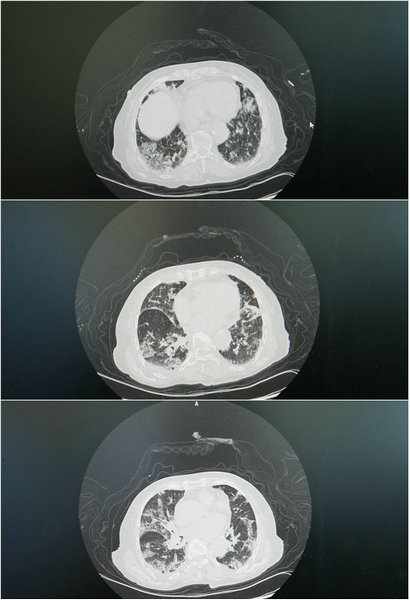

治疗前肺部CT显示

曹奶奶病情非常严重,核酸阳性、高热不退、呼吸困难、精神恍惚,嗜睡症状明显,血氧仪显示血氧饱和度83%,王岩主任看到家属带来的肺部CT后,考虑到曹奶奶肺炎为病毒、细菌混合感染,立即为曹奶奶做了全面检查,利用面罩吸氧,给予抗凝药物、激素药物治疗和营养支持,以及相关对症治疗的同时,还是向家属下达了病危通知书,王岩主任安排技术过硬的护士组成护理组,对曹奶奶进行一级护理,病房也是离护士站最近的,随时准备应对突发状况。

完善相关检查过后,曹奶奶的肺部CT显示:炎症非常严重!在紧急情况下,王岩主任邀来巡诊医师组呼吸内科专家顾泽鑫等专家进行集体会诊。